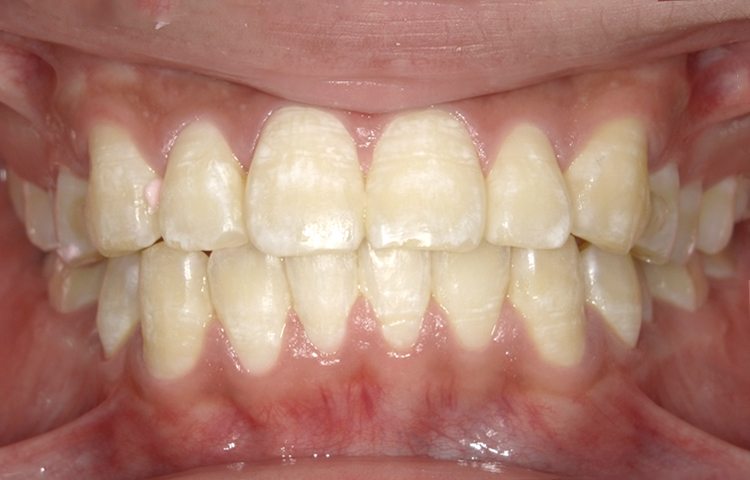

症例4

治療前

治療後

| 主訴 | 右上1番出ている 上のみ部分矯正希望 |

|---|---|

| 治療 期間 |

約8ヶ月 |

| 治療費 | 220,000円(税込)/調整費用別途 |

| 治療 内容 |

上の前歯部にワイヤーを着けて進めていく、プチ矯正で施術。 |

| 治療の リスク |

奥歯を動かさないので、前に出して並べていく。 歯と歯が移動するスペースを作るので、知覚過敏の症状がまれにでる。 装置による清掃の難しさから、歯肉炎や歯周病、虫歯の進行がするリスクが高まる。 歯を動かすことで、歯茎が下がるリスクある。 矯正終了後は、リテーナーを使用し、後戻りを防ぐ必要がある。 |